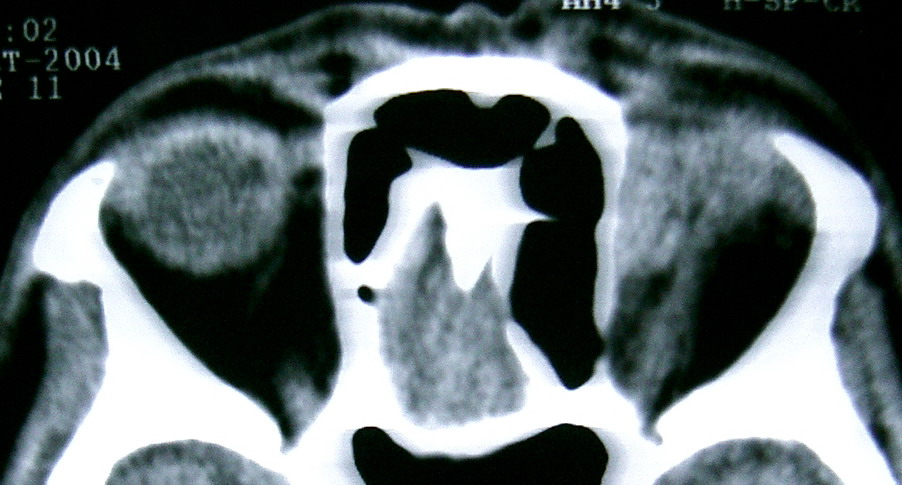

眼眶冠扫,平扫CT: 左眼球内上方可见不规则软组织块影,大小约2.5*1.0CM,与邻近组织分界不清,相邻之内直肌、上直肌增粗,眼环正常,眶壁骨质无破坏,左上颌窦底部可见粘膜增厚,其余副鼻窦未见异常。 IMP:1,左眼眶肿物;2,左上颌窦炎